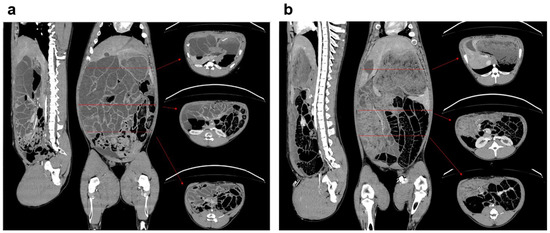

3.1. General Model Characteristics and Pathology